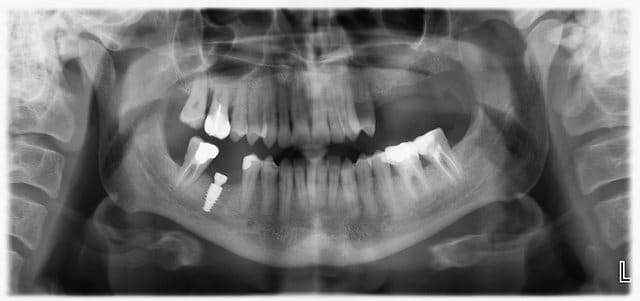

...implant posé hier matin... 5*10mm

A la fin du serrage manuel, douleurs du patient, je m'arrête, dévisse d'un quart de tour, termine l'intervention, prend la pano que vous voyez plus bas...

Donc je redévisse l'implant pour qu'il "remonte d'un millimètre" et je laisse comme ça.

30/10/2012 à 12h37

disons que t'as pas les 2 mm de sécurité prévus par le principe de précaution.

là je crois que déposer est la plus sage des solutions.

à part si t'es sûr que c'est pas juste une superposition de la panoramique mais il faudrait alors une 3D pour l'évaluer.

1° Faire rétro-alvéolaire et 3D pour voir si vraiment le nerf est atteint

J'ai fait des tests de sensibilités sur toute la zone d'inervation, il avait des sensation douloureuses aux piqures de partout. Atténuées certes mais elles étaient là. J'ai refais un radio rétro-alv (pas de cone beam au cab) on voit nettement l'implant à un bon mm au dessus du canal (et oui, je l'avais dévissés suite à la pano que vous voyez dans le premier post).

J'opte donc pour une simple compression du nerf, levée par le dévissage de l'implant, qui devrait s'attenuer avec le temps. Reste à savoir combien de temps...